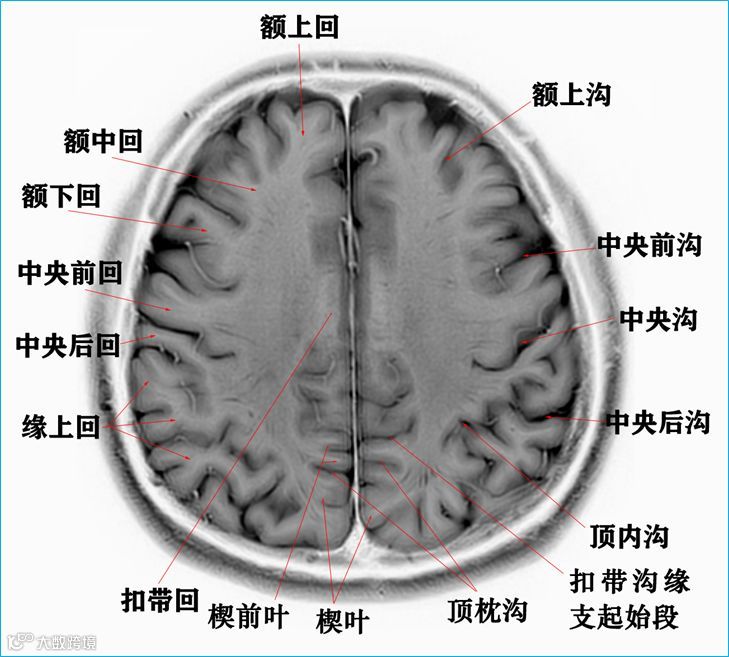

在T2WI反相图学下的颅脑断层解剖(吴晓安老师亲自手动标准)以及标本断层解剖,满满干货,坐在小板凳上,一起学习吧……